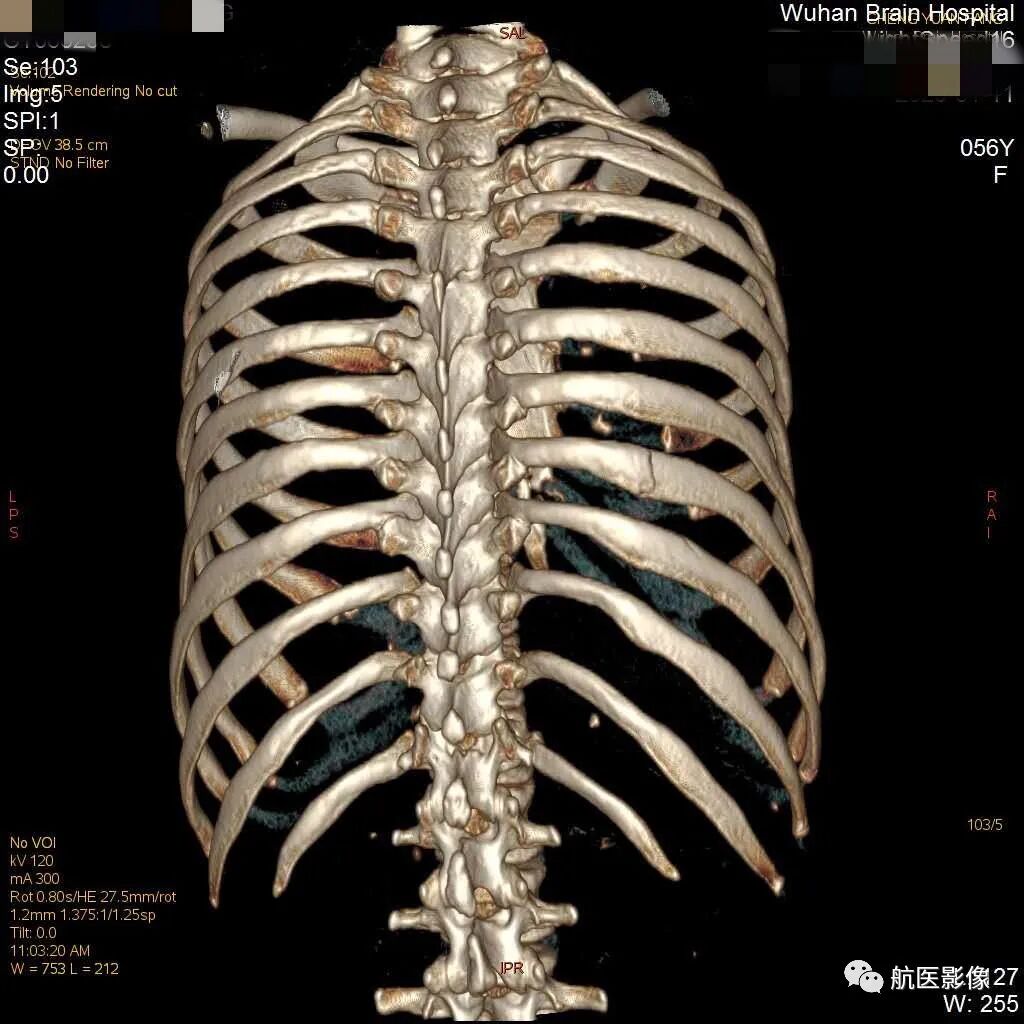

双侧肋骨共有12对,解剖形态不规则呈半弧形,由于肋骨解剖特点的复杂性,其走行的特殊性且环绕呈圆桶形,肋弓弯曲大,和前后多脏器互相重叠,故肋骨X摄片不易清楚显示细微、无明显移位的肋骨骨折,而横断面CT限于连续性、定位性不佳,不易确定具体肋骨骨折根数,而三维成像可将全部肋骨完整立体再现,并且可进行旋转观察,定位效果好,对肋骨骨折的显示具有重要意义,肋骨骨折的根数、骨折的类型对法医学鉴定结果影响尤其重要。

多层螺旋CT具有快速连续的扫描方式和容积性数据采集的特点,并具有多角度、多平面重组的后处理功能,能任意角度地旋转观察损伤部位情况,识别细微的肋骨骨折;CT扫描横轴位可显示骨折,但不能显示骨折全程。

VR是通过容积数据时所有像素总合的图像显示,利用了所有扫描信息,是一种较高形式的重建方式,并能通过任意手工选择层面,任意方位进行切割和旋转,较为满意地显示出骨折线、移位,是一种对骨折后处理较常用的CT后处理技术。VR三维重建图像提供近似解剖结构的图像,定位准确,空间立体感强。MPR可行冠状、矢状和轴位重建图像,对胸部损伤行多剖面观察,可清楚显示断端周围软组织肿胀;能随时在VR、MPR、骨窗及肺窗间进行转换。